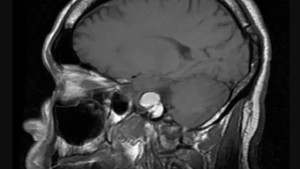

Lipoprotein tỉ trọng thấp (LDL) thường được gọi là cholesterol xấu. Nó có nhiệm vụ mang cholesterol đến các động mạch. Khi lượng LDL cholesterol tăng lên quá cao, chúng sẽ bắt đầu tích tụ trên thành động mạch và tạo nên các mảng bám cholesterol. Các mảng bám này sẽ dần dần làm cho lòng động mạch bị thu hẹp lại, gây cản trở sự lưu thông máu và tăng nguy cơ hình thành cục máu đông. Nếu cục máu đông bít động mạch trong tim hoặc não thì sẽ gây ra nhồi máu cơ tim hoặc tai biến mạch máu não.

- Tai biến mạch máu não